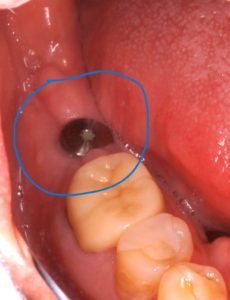

歯石をとらなかったら。画像あり

歯と歯茎の間、生え際には皆、隙間があります。

ここに細菌が住み着くなどして蓄積して石灰化して

除去できないとなるとこうなります。

こんな大事になってからの来院になってしまったら

大変な思いするのはあなたです。

幼いころからリスクを積み重ねて、こうなります。

なんでこうなったと思いますか?

「知識、関心がなかった、後回しにした。」

「自分の口のこと理解せずその場しのぎの治療を繰り返した。」

重度歯周病です。治療しましょう。